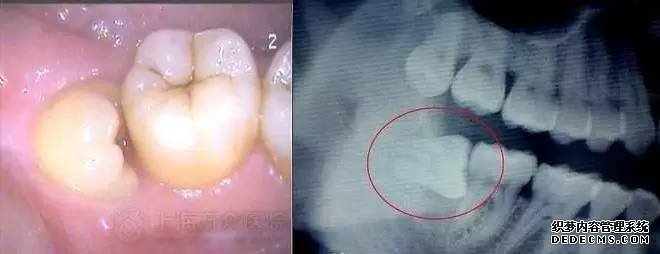

智齿,也就是最后一颗磨牙,一般在青春期以后开始长,甚至更晚。当然也有一部分人不长。但是由于人类进化的原因,下颌体积逐渐减小,很多人的下颌空间不足以生长出智齿,那么就会阻生。当智齿阻生或者生长方向不正时,经常会顶坏前面的第二磨牙或者引起智齿冠周炎,从而引起肿痛、口臭等症状。

如果智齿位置及方向长得正,而且有良好的咬合关系,就可以考虑保留,但是如果像下面图片所示,牙齿朝前生长,那就要及早拔掉。